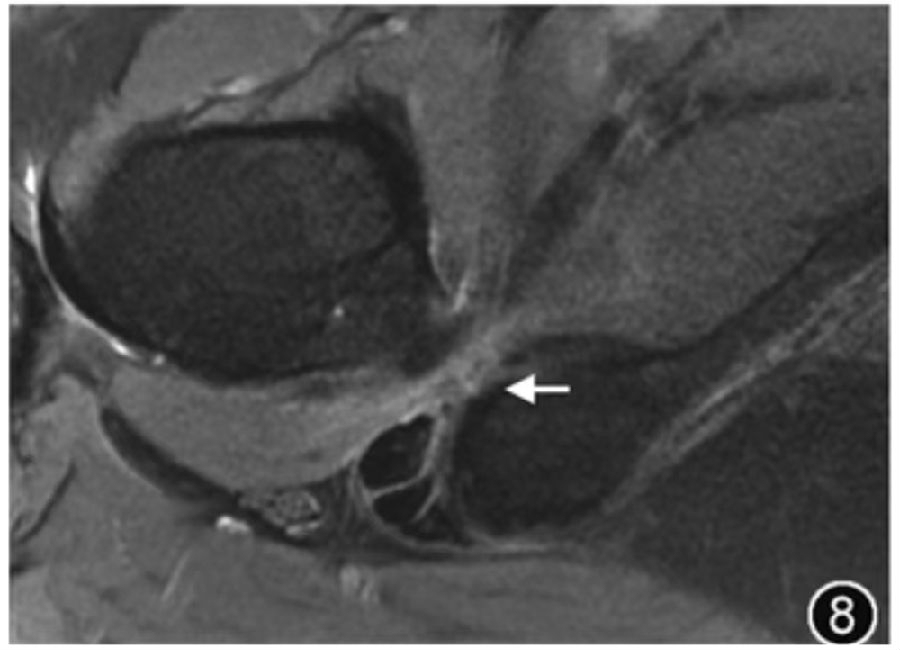

7.坐骨股骨撞击综合征:坐骨股骨撞击综合征是由于股骨小转子和坐骨结节之间的股方肌受到撞击而导致臀部深部疼痛,由于坐骨股骨间隙变窄所致。在有症状的患者中,如果坐骨股骨间隙异常狭窄并且股方肌水肿伴或不伴萎缩,则提示可能存在坐骨股骨撞击综合征。对于判定坐骨股骨间隙狭窄的临界值目前尚存在争议,可能是由于不同地域人群解剖差异及不同测量方法导致,但目前普遍认为,坐骨股骨间隙<15 mm 和/或股方肌间距<10mm,发生坐骨股骨撞击的概率较高(图8)。如果在没有坐骨股骨间隙狭窄的情况下看到股方肌水肿,则不应考虑为坐骨股骨撞击,应考虑股方肌拉伤、撕裂或去神经支配等原因。

图8 坐骨股骨撞击MRI图像。横断面T2WI示股骨坐骨间隙狭窄,间隙为6.4 mm,同时伴有股方肌水肿(↑)